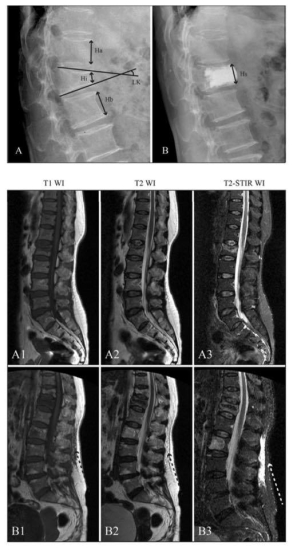

Para determinar la incidencia y los factores de riesgo del dolor lumbar residual en pacientes con fractura por compresión vertebral osteoporótica (OVCF) después del tratamiento con cifoplastia percutánea (PKP), realizamos un análisis retrospectivo de datos prospectivos.

La incidencia de dolor residual de espalda posoperatorio fue del 7,8% entre 809 pacientes con fractura por compresión vertebral osteoporótica (OVCF) después de PKP. La presencia de una hendidura intravertebral por vacío, edema de fascia posterior, violaciones de las articulaciones facetarias y una distribución de cemento separada se identificaron como factores de riesgo independientes para el dolor de espalda residual.